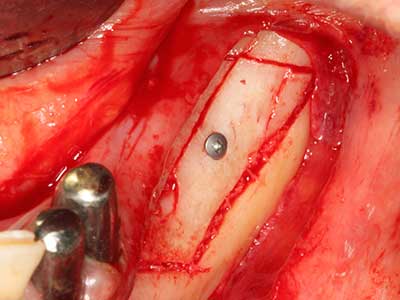

Piezo surgery has additional advantages when harvesting bone blocks. In addition to the high precision with osteotomy described above, the use of the thin saw tips specifically minimizes loss of material. Greater loss of material during harvesting can be expected with the thicker instrument tips, particularly when using Lindemann drills (Lakshmiganthan, Gokulanathan et al. 2012). The basal separation, which is necessary particularly for retromolar block transplants, is simplified by specially designed rectangular saws, with the result that piezo surgery is viewed as a precise, simple and safe procedure for harvesting retromolar bone blocks (Happe 2007) (Fig. 1-12).